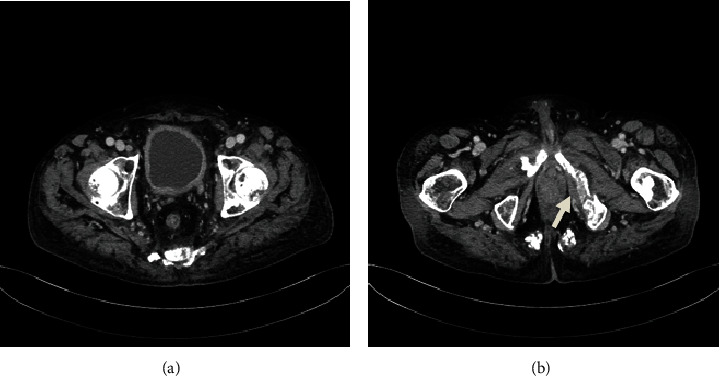

A 65-year-old man was diagnosed with bladder cancer invading the prostate and penis and multiple bone metastases. He underwent palliative radiation (30 Gy/10 fr) through vertebral bones (Th3 and Th12-L5) and pelvic bones for pain control. The patient received pembrolizumab therapy after three courses of gemcitabine and cisplatin therapy. CT four weeks after starting pembrolizumab therapy showed that both the primary and metastatic lesions had notably reduced in size, and no new lesion was detected. He subsequently fell, resulting in a femoral neck pathological fracture, and underwent hemiarthroplasty. Pathological examination of the pathological fracture site revealed no residual tumor tissue.